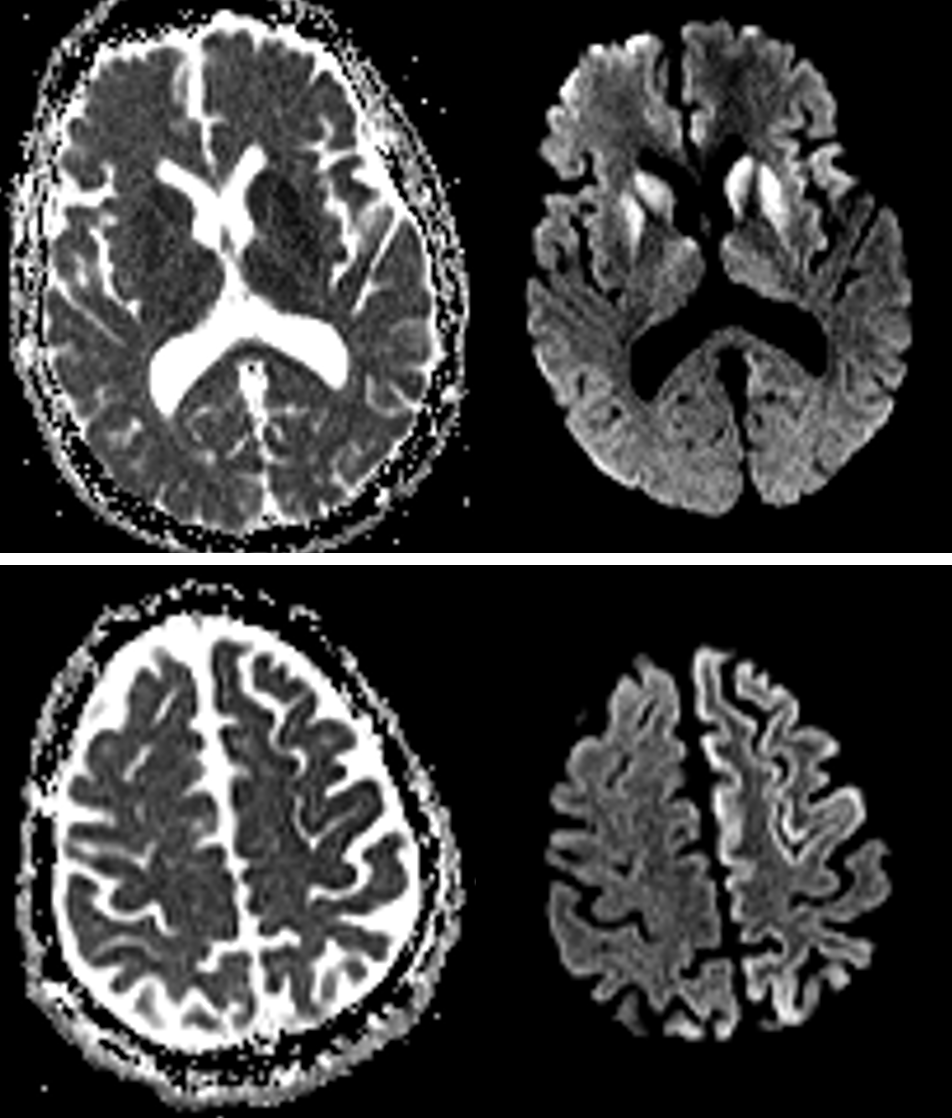

Age: 62

Sex: Male

Indication: Worsening gait abnormality

Creutzfeldt-Jakob disease (CJD)

Sample ReportRestricted diffusion and T2/FLAIR signal hyperintensity involving the bilateral corpus striatum as well as patchy involvement of the cerebral cortex bilaterally, particularly in the left frontal lobe and left cingulate gyrus. Additional faint restricted diffusion involving the bilateral thalami. This appearance raises particular concern for Creutzfeldt-Jakob disease (CJD) in the clinical context of progressive neurologic decline.